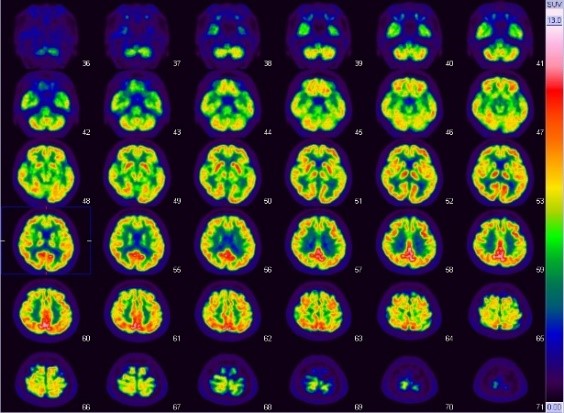

FDG-PET検査

この検査は、てんかんの病巣診断、心サルコイドーシスの診断、早期胃がんを除く全ての悪性腫瘍・悪性リンパ腫の診断等に有用とされています。当院では主にてんかんの方の検査を多く行っていますが、その他の上記疾患の検査も行っています。

使用する放射性医薬品は18F-FDGです。当院では投与直前から調光下で安静にベッドに横になっていただき、投与後は頭部検査では45分後から15分程度、全身では60分後から30分程度、心臓では全身の撮像後に15分程度の撮像を行います。